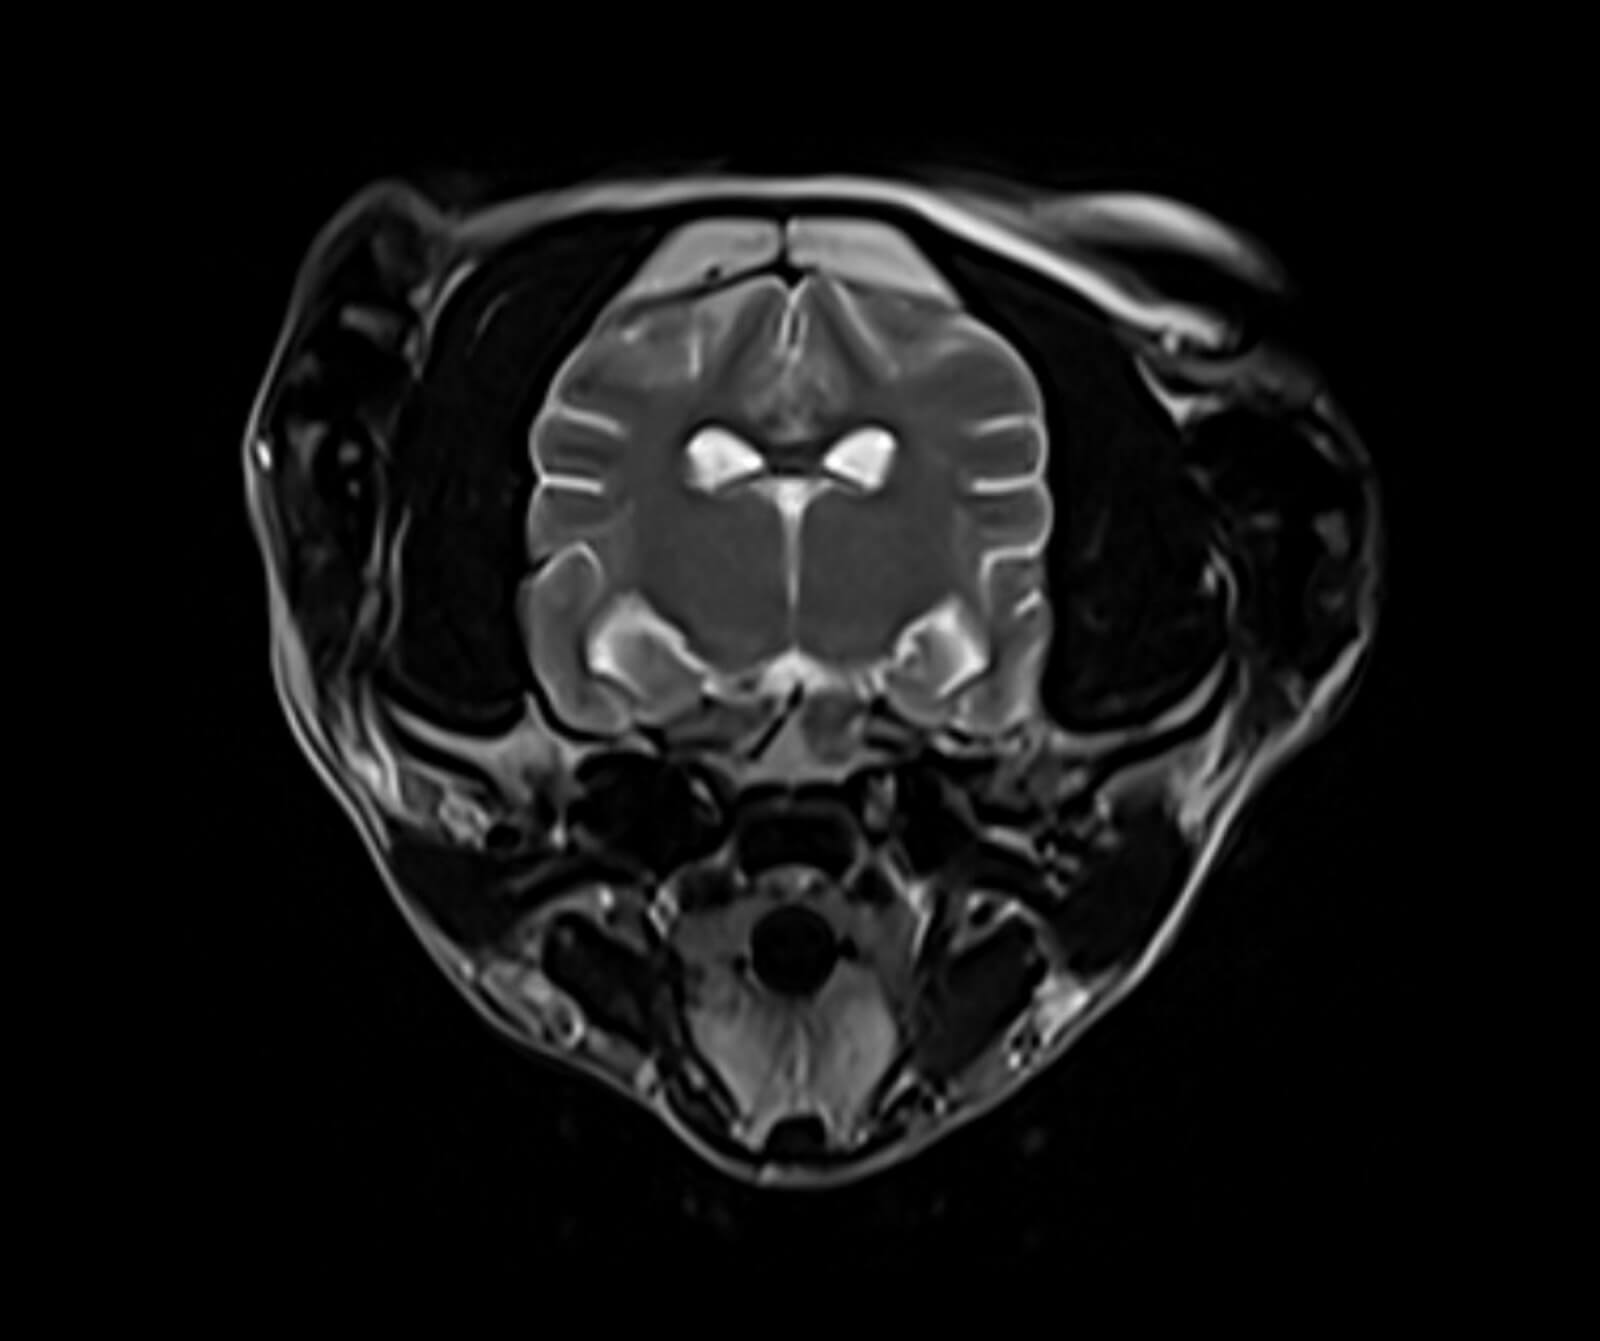

Manyetik Rezonans Görüntüleme (MR), sevimli dostlarımızın vücudundaki doku ve organların yüksek çözünürlükte, ayrıntılı ve güvenli biçimde değerlendirilmesini sağlayan ileri düzey bir tanısal görüntüleme yöntemidir. Radyasyon içermeyen bu yöntem, özellikle yumuşak dokuların detaylı incelenmesi gereken durumlarda en değerli tanı araçlarından biridir.

Veteriner hekimliğinde MR; beyin, omurilik, sinir sistemi, kas-iskelet sistemi ve iç organ hastalıklarının değerlendirilmesinde kritik rol oynar. Kemik yapılar dâhil olmak üzere vücudun tüm bölgeleri MR ile ayrıntılı şekilde incelenebilir.

• Beyin ve spinal kord patolojileri

• Spinal kord incelemeleri